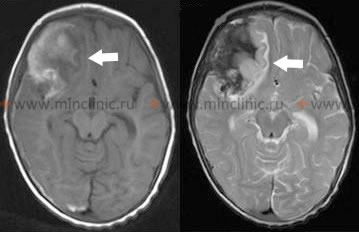

დიაგნოზი ჩვეულებრივ დასტურდება გადაუდებლად თავის ტვინის განმეორებითი კომპიუტერული ტომოგრაფიის (კტ) სკანირებით, რომელიც ტიპიურად აჩვენებს სუბარაქნოიდულ სივრცეში, პარკუჭებში ან ტვინის პარენქიმაში სისხლის ახალ ან გაზრდილ რაოდენობას წინა სკანირებებთან შედარებით [1, 4].

| ანევრიზმის განმეორებითი გასკდომა | LOC-ის (ცნობიერების დონის) უეცარი, კატასტროფული დაქვეითება, ხშირად ძლიერი თავის ტკივილის მატება, ახალი დეფიციტები. უმაღლესი რისკი ადრეულ ეტაპზე ანევრიზმის იზოლირებამდე. | თავის განმეორებითი კტ აჩვენებს ახალ/გაზრდილ სისხლჩაქცევას (SAH, IVH, ICH). საჭიროა გადაუდებელი ანგიოგრაფია, თუ არ არის იზოლირებული. |